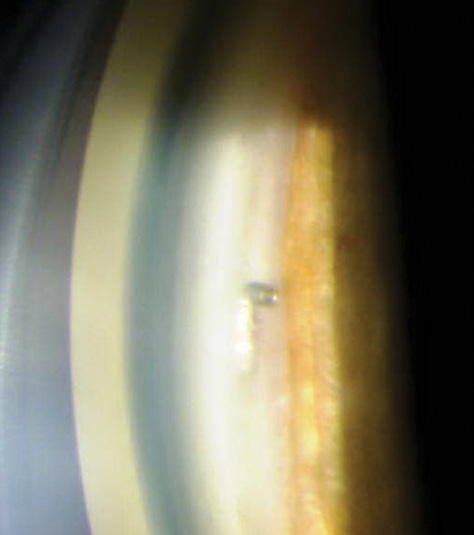

From my perspective, the concept of withholding MIGS training from residents is shortsighted. Although MIGS technologies continue to evolve, their excellent safety profile and value are undeniable. With proper supervision, residents can certainly be successfully trained to perform MIGS procedures. I would argue that learning these procedures may actually make residents better clinicians. This education will enhance their gonioscopy skills (Figure), and it will prompt them to obtain more thorough medical histories in order to ascertain whether patients are adhering to prescribed glaucoma therapy and what their quality-of-life goals are.

Figure. The iStent is visible on gonioscopy.